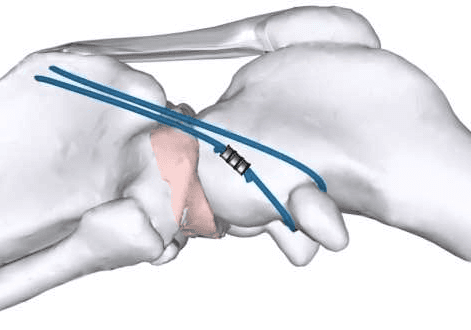

Tight Rope

This technique is similar to the LFTS in that a heavy-duty suture is placed outside the joint to mimic the ligament’s function. The major differences are the suture material used in the Tight Rope is significantly stronger which is then secured with additional metal implants.

The Tight Rope is used in dogs too large for an LFTS. Recovery time is 8-10 weeks.